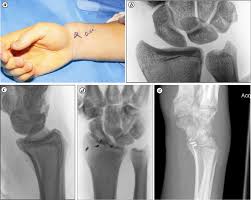

(minor sprain) high signal is seen medial (superficial) to the ligament, which looks normal grade 2: Athletes are particularly prone to wrist sprain. A tear can be serious and can, if left untreated, as is often the case, lead to instability of the wrist, pain, stiffness, loss of grip strength and irreversible osteoarthritis. Complete tear of the ligament. Grade 2 sprains — the ligament is stretched, and it could be partially torn. Grade 3 sprained wrist (severe) this is the most serious type of wrist sprain. If you are experiencing swelling or pain in your wrist, the cause could be a torn wrist ligament. Wrist ligaments are stretched and have microscopic tears; There are two major types of wrist sprains that are based on location. The highly trained hand and wrist specialists at hand surgery specialists of texas specialize in treating torn ligaments in the wrist. A grade 1 injury is described as ligament stretching but no tear and minimal bleeding. When the ligaments in the wrist are stretched or have tiny microscopic tears, it is called a mild (grade i) wrist sprain. Pain worsens when bending the wrist sideways so the little finger moves towards the forearm (called ulnar deviation).

The ligaments have fairly low vascularity (blood supply) that is why it takes much more time to heal. This is a severe sprain with a complete tear of the ligament. Intermediate sprain with partial thickness tear of the ligament Wrist ligament tears may be classified as: The scapholunate ligament connects the scaphoid to the lunate. There are two major types of wrist sprains that are based on location. A grade 1 (mild) sprain usually involves stretching of a ligament. Grade 2 sprains can involve a ligament being partly torn, which can affect your range of movement grade 3 sprains are when the ligament is torn, sometimes fracturing the bone as it tears (avulsion fracture). Although there are many ligaments and injuries in the wrist, a scapholunate ligament tear is the most commonly injured. The most important part of the ligament is on the back (dorsal side) of the wrist. Wrist ligaments are stretched and have microscopic tears; A grade 3 (severe) sprain involves a complete rupture of one or more ligaments that may pull off a bone fragment (avulsion fracture). This is a mild sprain that damages the ligament but does not cause significant tearing.